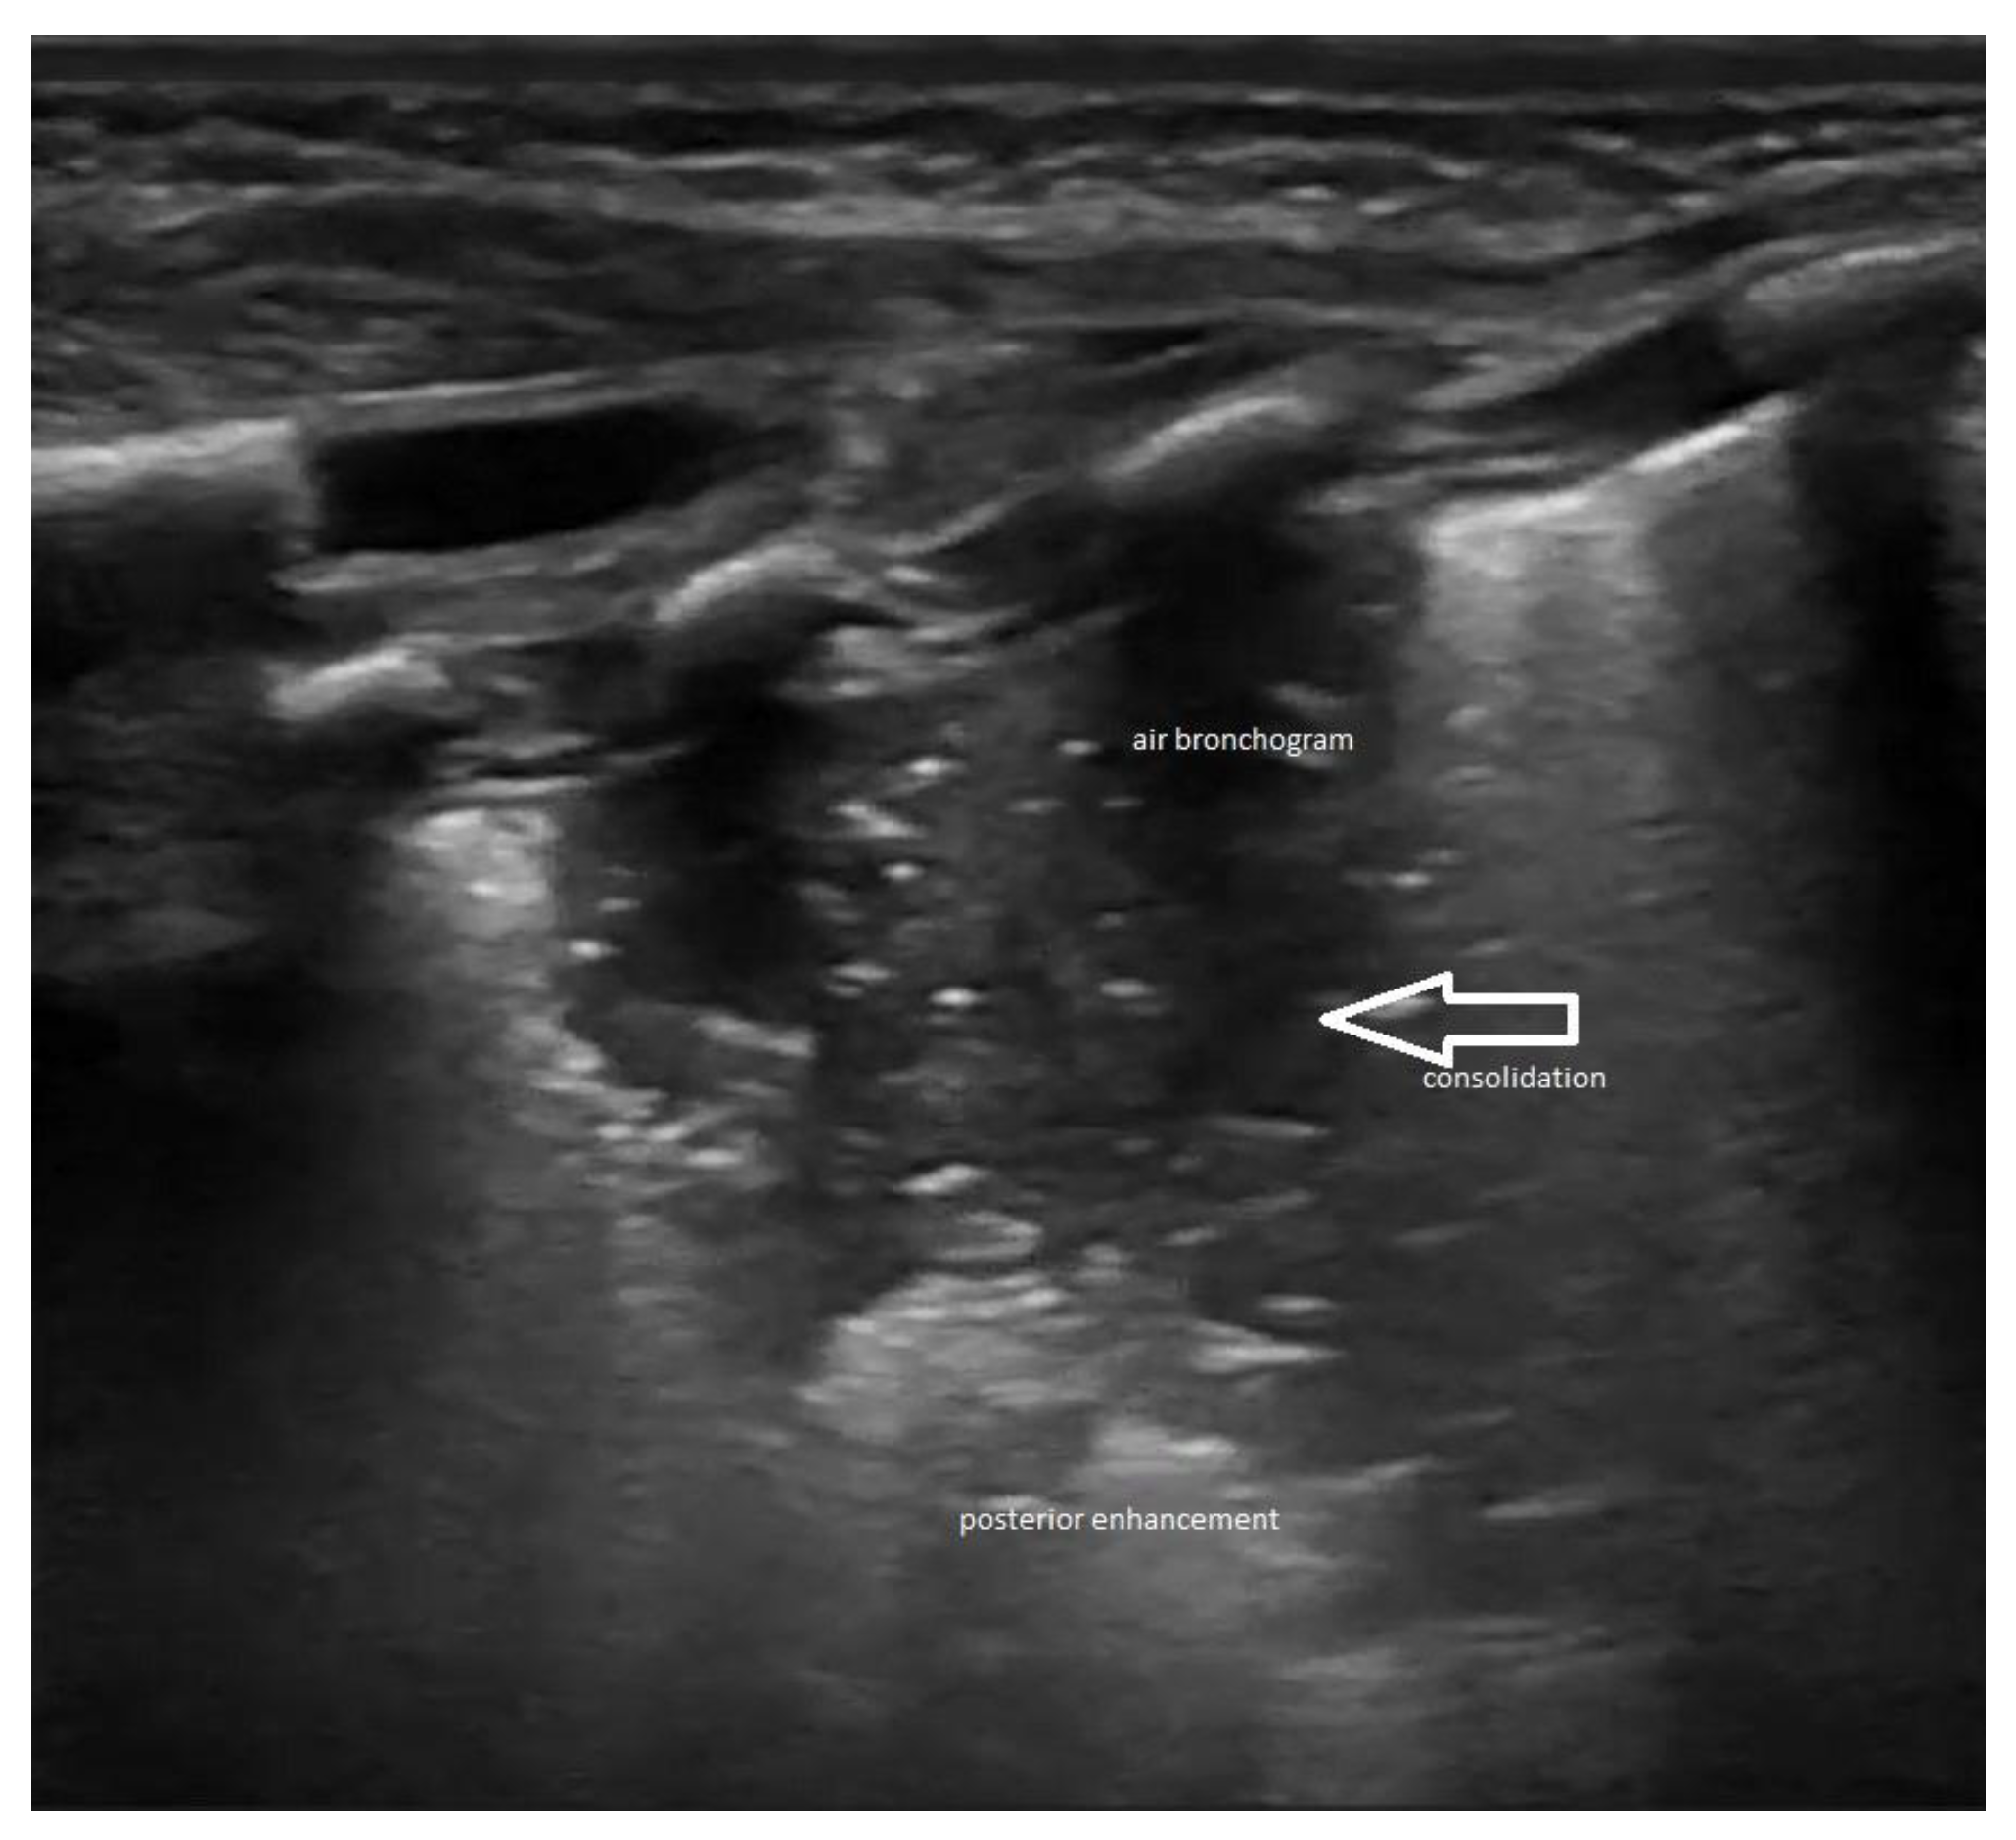

Lung ultrasound